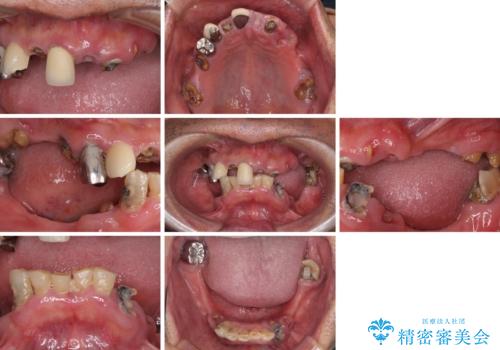

- どこで咬んでよいのか分からないとのことで来院された患者様です。

歯冠の崩壊した奥歯と、前歯の一部でした咬み合うことができず、入れ歯も試したものの、装着することができなかったようです。

全顎的にインプラント補綴を行うことも検討しましたが、費用面から、インプラントを土台とした入れ歯(インプラント・オーバーデンチャー)による補綴治療を行うこととしました。

入れ歯の固定源にはマグネットやロケーター、ボールアタッチメントなどがありますが、お住まいが遠方であることや、奥歯に力がかかりやすいことから、維持力が強く、メインテナンスが行いやすいロケーターを採用しました。